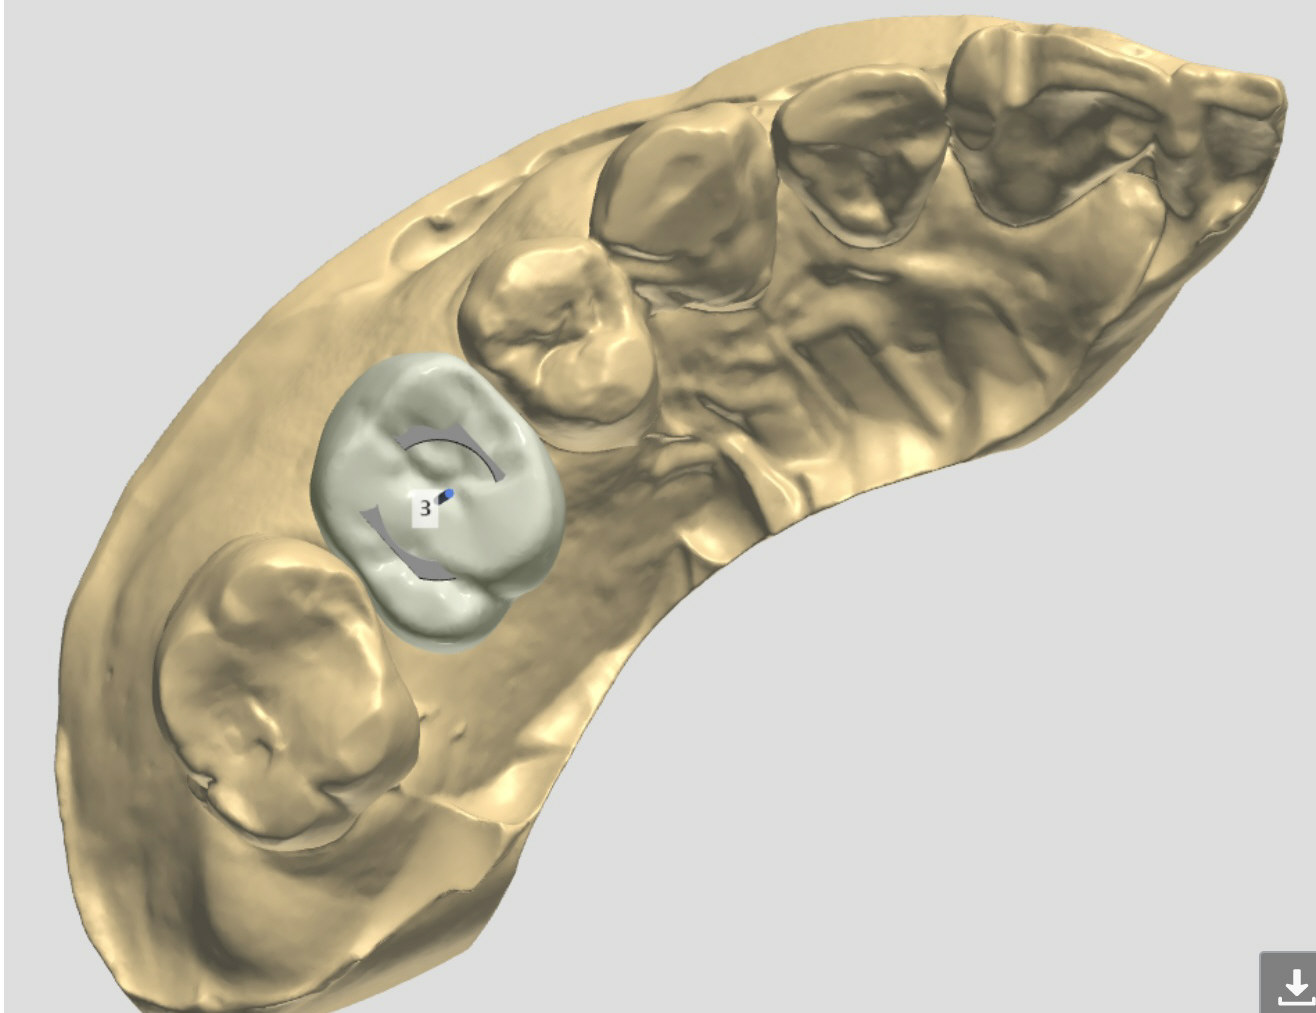

Wide Bone

A 52-year-old man requests implant at #3 and 31 a few months post socket preservation.